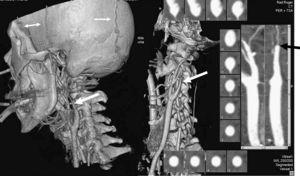

La angiografía computarizada constató en todos los casos la detención del contraste al nivel del agujero magno sin visualizarse contraste en arterias vertebrales intracraneales. Al estudiar la circulación anterior se visualiza un afilamiento progresivo de las arterias carótidas internas en el cuello, comprobándose que el contraste se detiene en la porción petrosa carotídea, y demostrándose la ausencia de relleno de las arterias carótidas internas intracraneales. Se observa relleno de contraste en las diferentes ramas de las arterias carótidas externas (figs. 1-4).

Figura 2. Reconstrucción 3D en la que se observa flujo en la arteria carótida común y arterias vertebrales extracraneales, así como en las diversas ramas de la arteria carótida externa. Nótese el afilamiento de la arteria carótida interna (flecha gruesa). En el análisis de flujo de los vasos visualizados (marcado mediante línea puntos suspensivos en color blanco) se observa la desviación del flujo de la carótida primitiva hacia la carótida externa.

Figura 3. Reconstrucción 3D con supresión del hueso, donde se evidencia la parada del flujo en las arterias carótidas internas (flecha gruesa) y arterias vertebrales (flecha fina) a nivel extracraneal. Se visualizan las arterias carótidas externas y sus ramas (doble flecha).